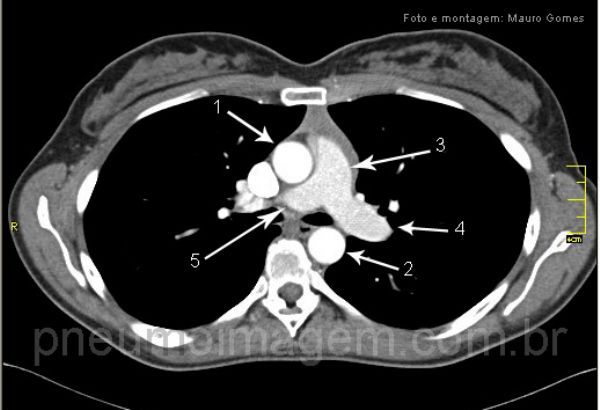

De25-10-2010S4I53.jpg)

(1) aorta ascendente;

(2) aorta descendente;

(3) tronco da artéria pulmonar;

(4) artéria pulmonar esquerda;

(5) artéria pulmonar direita.

Chaves:

(1) ascending aorta,

(2) descending aorta,

(3) pulmonary artery,

(4) left pulmonary artery,

(5) the right pulmonary artery.